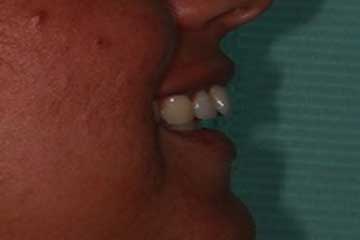

Con protesi fissa superiore e protesi fissa inferiore

I denti irrecuperabili dell'arcata superiore ed inferiore del paziente di anni 65

sono stati sostituiti da 10 impianti, cioè protesi radicolari endo-ossee che sostengono le protesi fisse superiore ed inferiore.